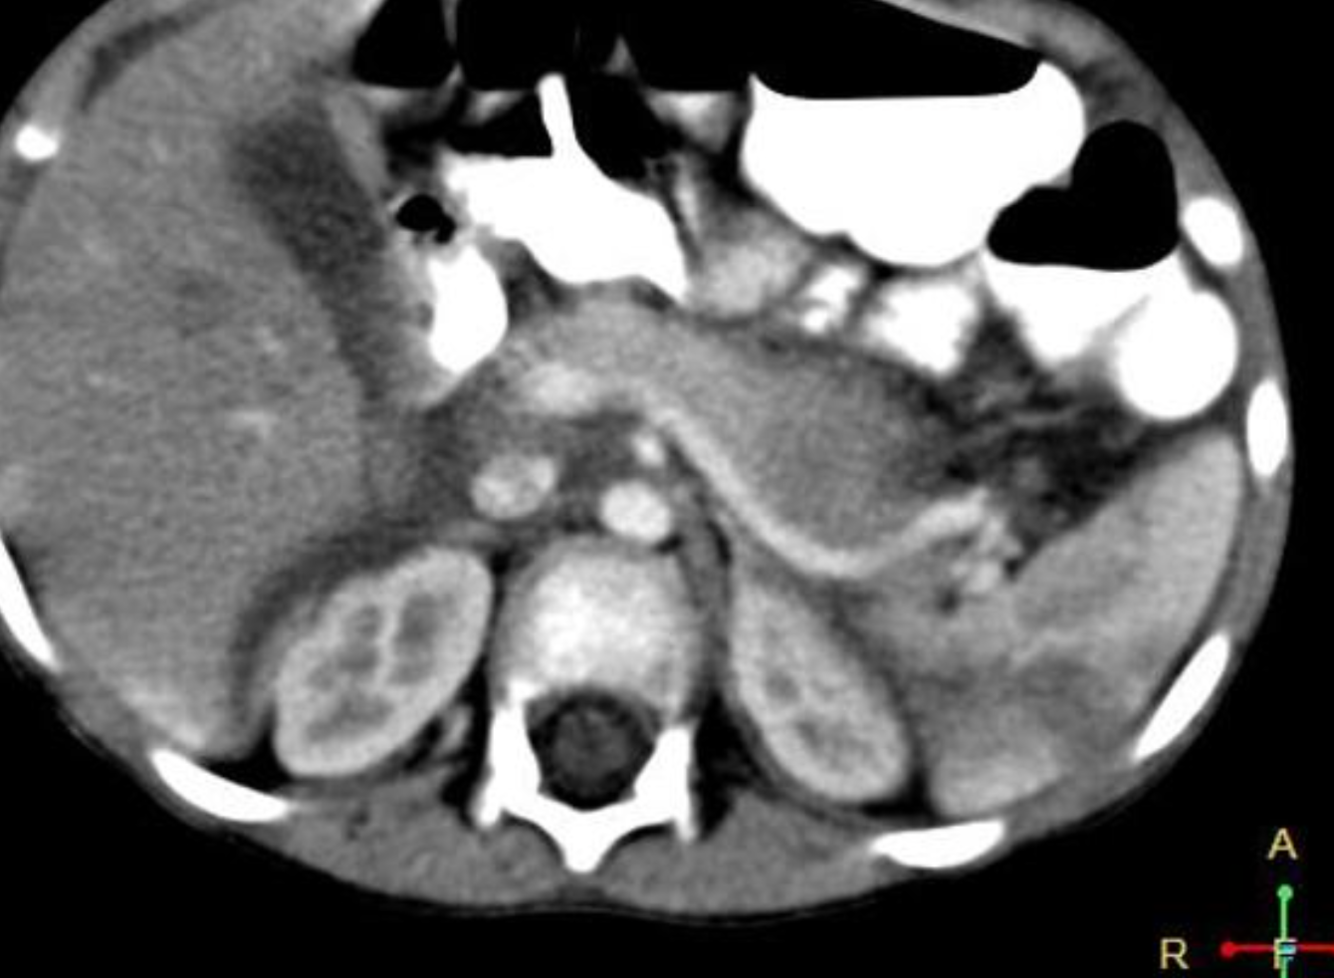

There is inversion of some abdominal structures (liver, spleen and stomach) with thoracic structures in normal position. Multiple splenules are seen on right hypochondrium. The study protocol was made for chest CT.

Case Discussion

Situs inversus partialis refers to any kind of incomplete organs inversion, like in this case. Malformations associations are more frequent in situs inversus partialis than in situs inversus totalis.